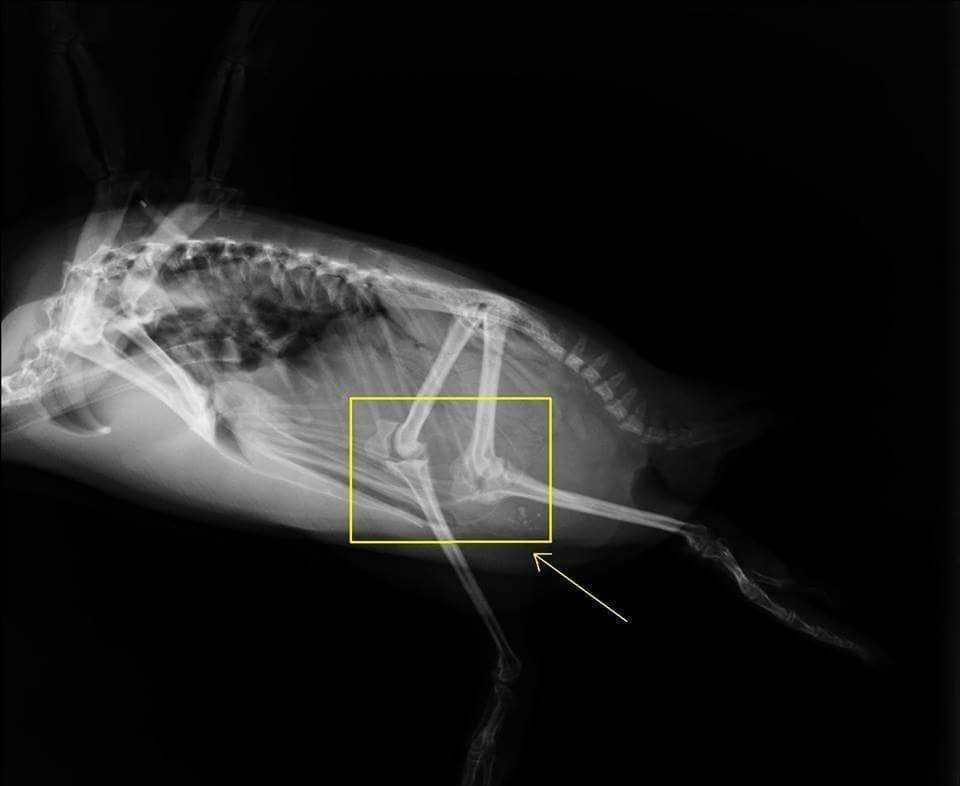

http://penguins.neaq.org/20...هل كنت تعلم ان للبطريق رُكَب ؟